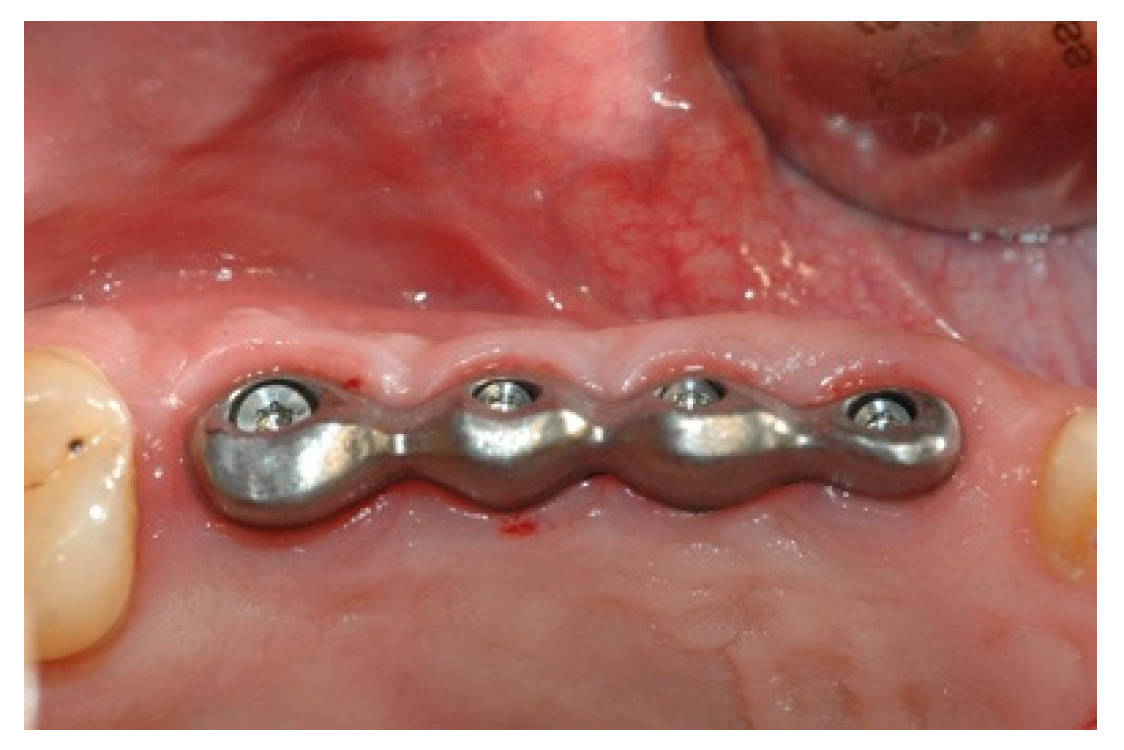

Once the mesostructure was made, it was checked to verify passive adaptation and its precise coupling with the arched fixtures (Figure 8 and Figure 9).

Figure 8. Mesostructure test.

Prosthesis 02 00023 g008

Figure 9. Mesostructure test.